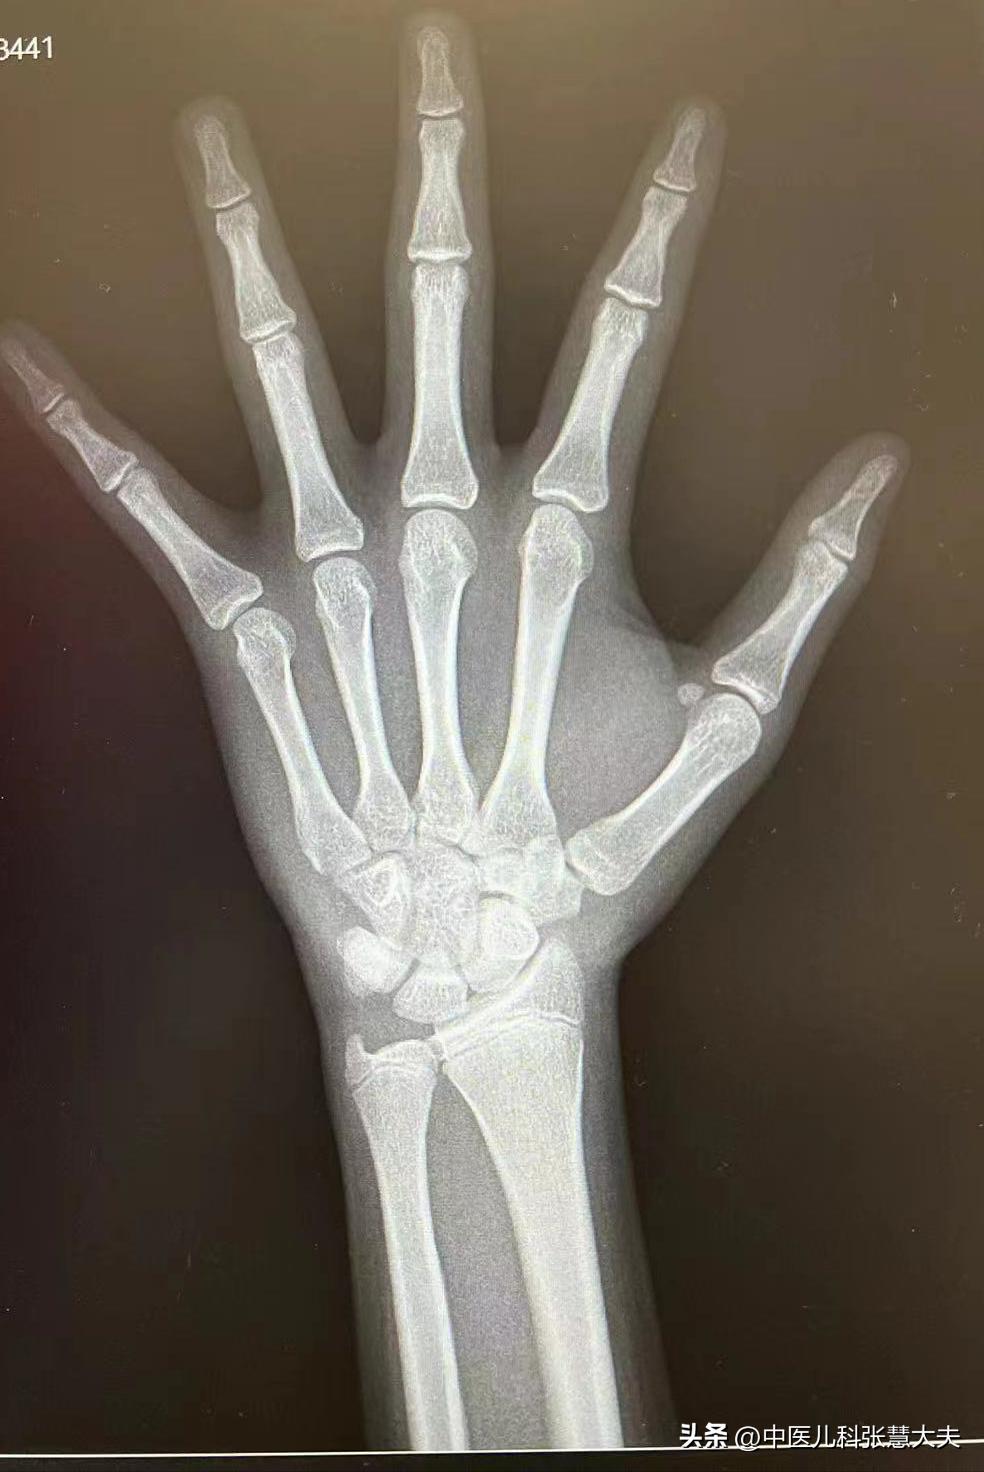

骨龄去哪儿查?怎么查?

专业的生长发育门诊,或者小儿内分泌都可以拍骨龄,也可以评估骨龄,因为评估骨龄需要时间,有的地方可能需要等等去拿结果。

通常来说,只要能拍X光的医院,都可以拍。只不过没有专业的大夫,拍完不会帮你评估。

拍骨龄片的时候,让孩子掌心向下平放,五指自然分开,肘部和手部要在一个水平线上,手指不能上翘或者下弯。

如果发现孩子身高偏矮,带孩子拍个骨龄片,一次几十块钱,是不是晚长,家长心里就有数了。